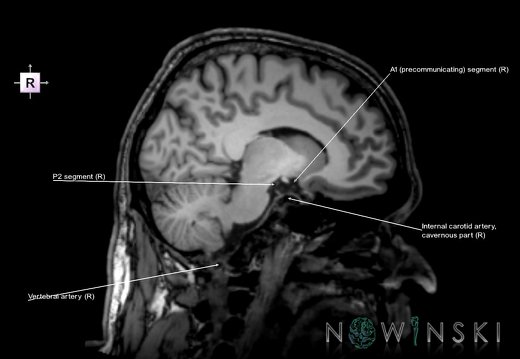

G6.T15.2.V2.P20.Intracranial arteries–Triplanar

G6.T15.2.V2.P20S.Intracranial arteries–Triplanar